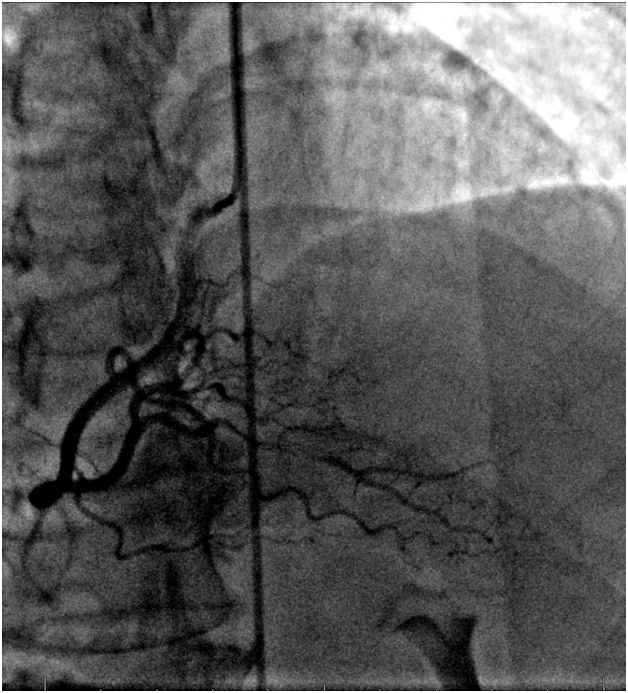

A 50years old lady with history of untreated hypertension presented with acute substernal chest pain, radiating to the center of her back following ingestion of cold water, associated with numbness in both upper extremities. Initial Electrocardiogram (ECG) showed inferior STEMI and the patient received loading doses of Aspirin and Clopidrogel. Cardiac enzymes were elevated with a Troponin-I of 26ng/ml. Emergent left heart catheterization was performed and did not reveal any obstructive coronary artery disease, yet the ostium of the right coronary was thought to have spasm and non-selective injection was performed without revealing any obvious abnormality. Hence, a Computerized Tomography (CT) aortography of the chest was ordered and aortic dissection was ruled out. A transthoracic echocardiogram revealed left ventricular ejection fraction (LVEF) of 50% with inferior wall and apico-septal hypokinesis. Due to the unexplained etiology of her presentation, the patient was transferred to a tertiary care hospital for further evaluation. Patient remained electrically and hemodynamically stable throughout her hospitalization despite the presence of intermittent chest pain episodes. This triggered a repeat left heart catheterization, which demonstrated spontaneous spiral dissection in the mid portion of the Posterior Descending Artery (PDA) (Figure 1) not previously seen by initial limited coronary angiography. Due to Concerns about the association of spontaneous dissection with Fibromuscular Dysplasia (FMD), an abdominal aortogram with bi-iliac angiogram was performed revealing right renal artery FMD (Figure 2).

Figure 1 Still frame image of right coronary artery terminating into a tortuous posterior descending artery where there is a distal dissection (blue arrow).